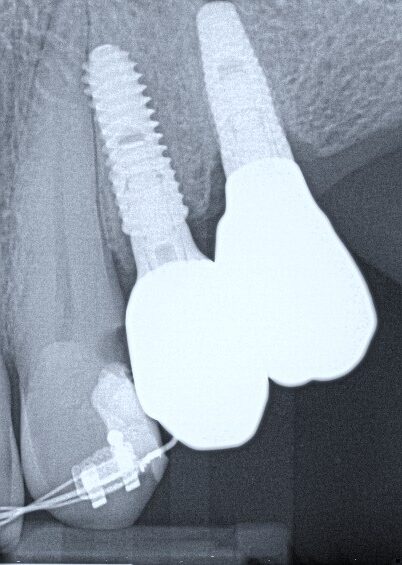

13. (Select ONE or MORE correct answer)

Which of the following is true regarding dental implant at site 2.6?